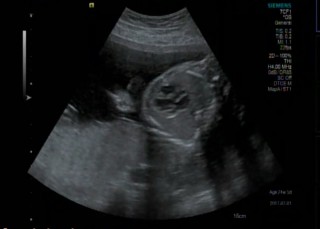

24w5d

BPD(児頭大横径)=64.3mm

AC(腹部周囲長)=203.8mm

FL(大腿骨長)=44.0mm

EFW(推定胎児体重)=833g

性別=男

心臓のエコー写真。

右室・右房・左室・左房異常なし。